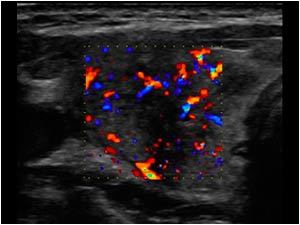

Amiodarone induced thyrotoxicosis

2 Types:

How to distinguish

1) Type I :

2) Type II:

How to distinguish betweent the two.

AIT - most common cases in iodine sufficient regions are: